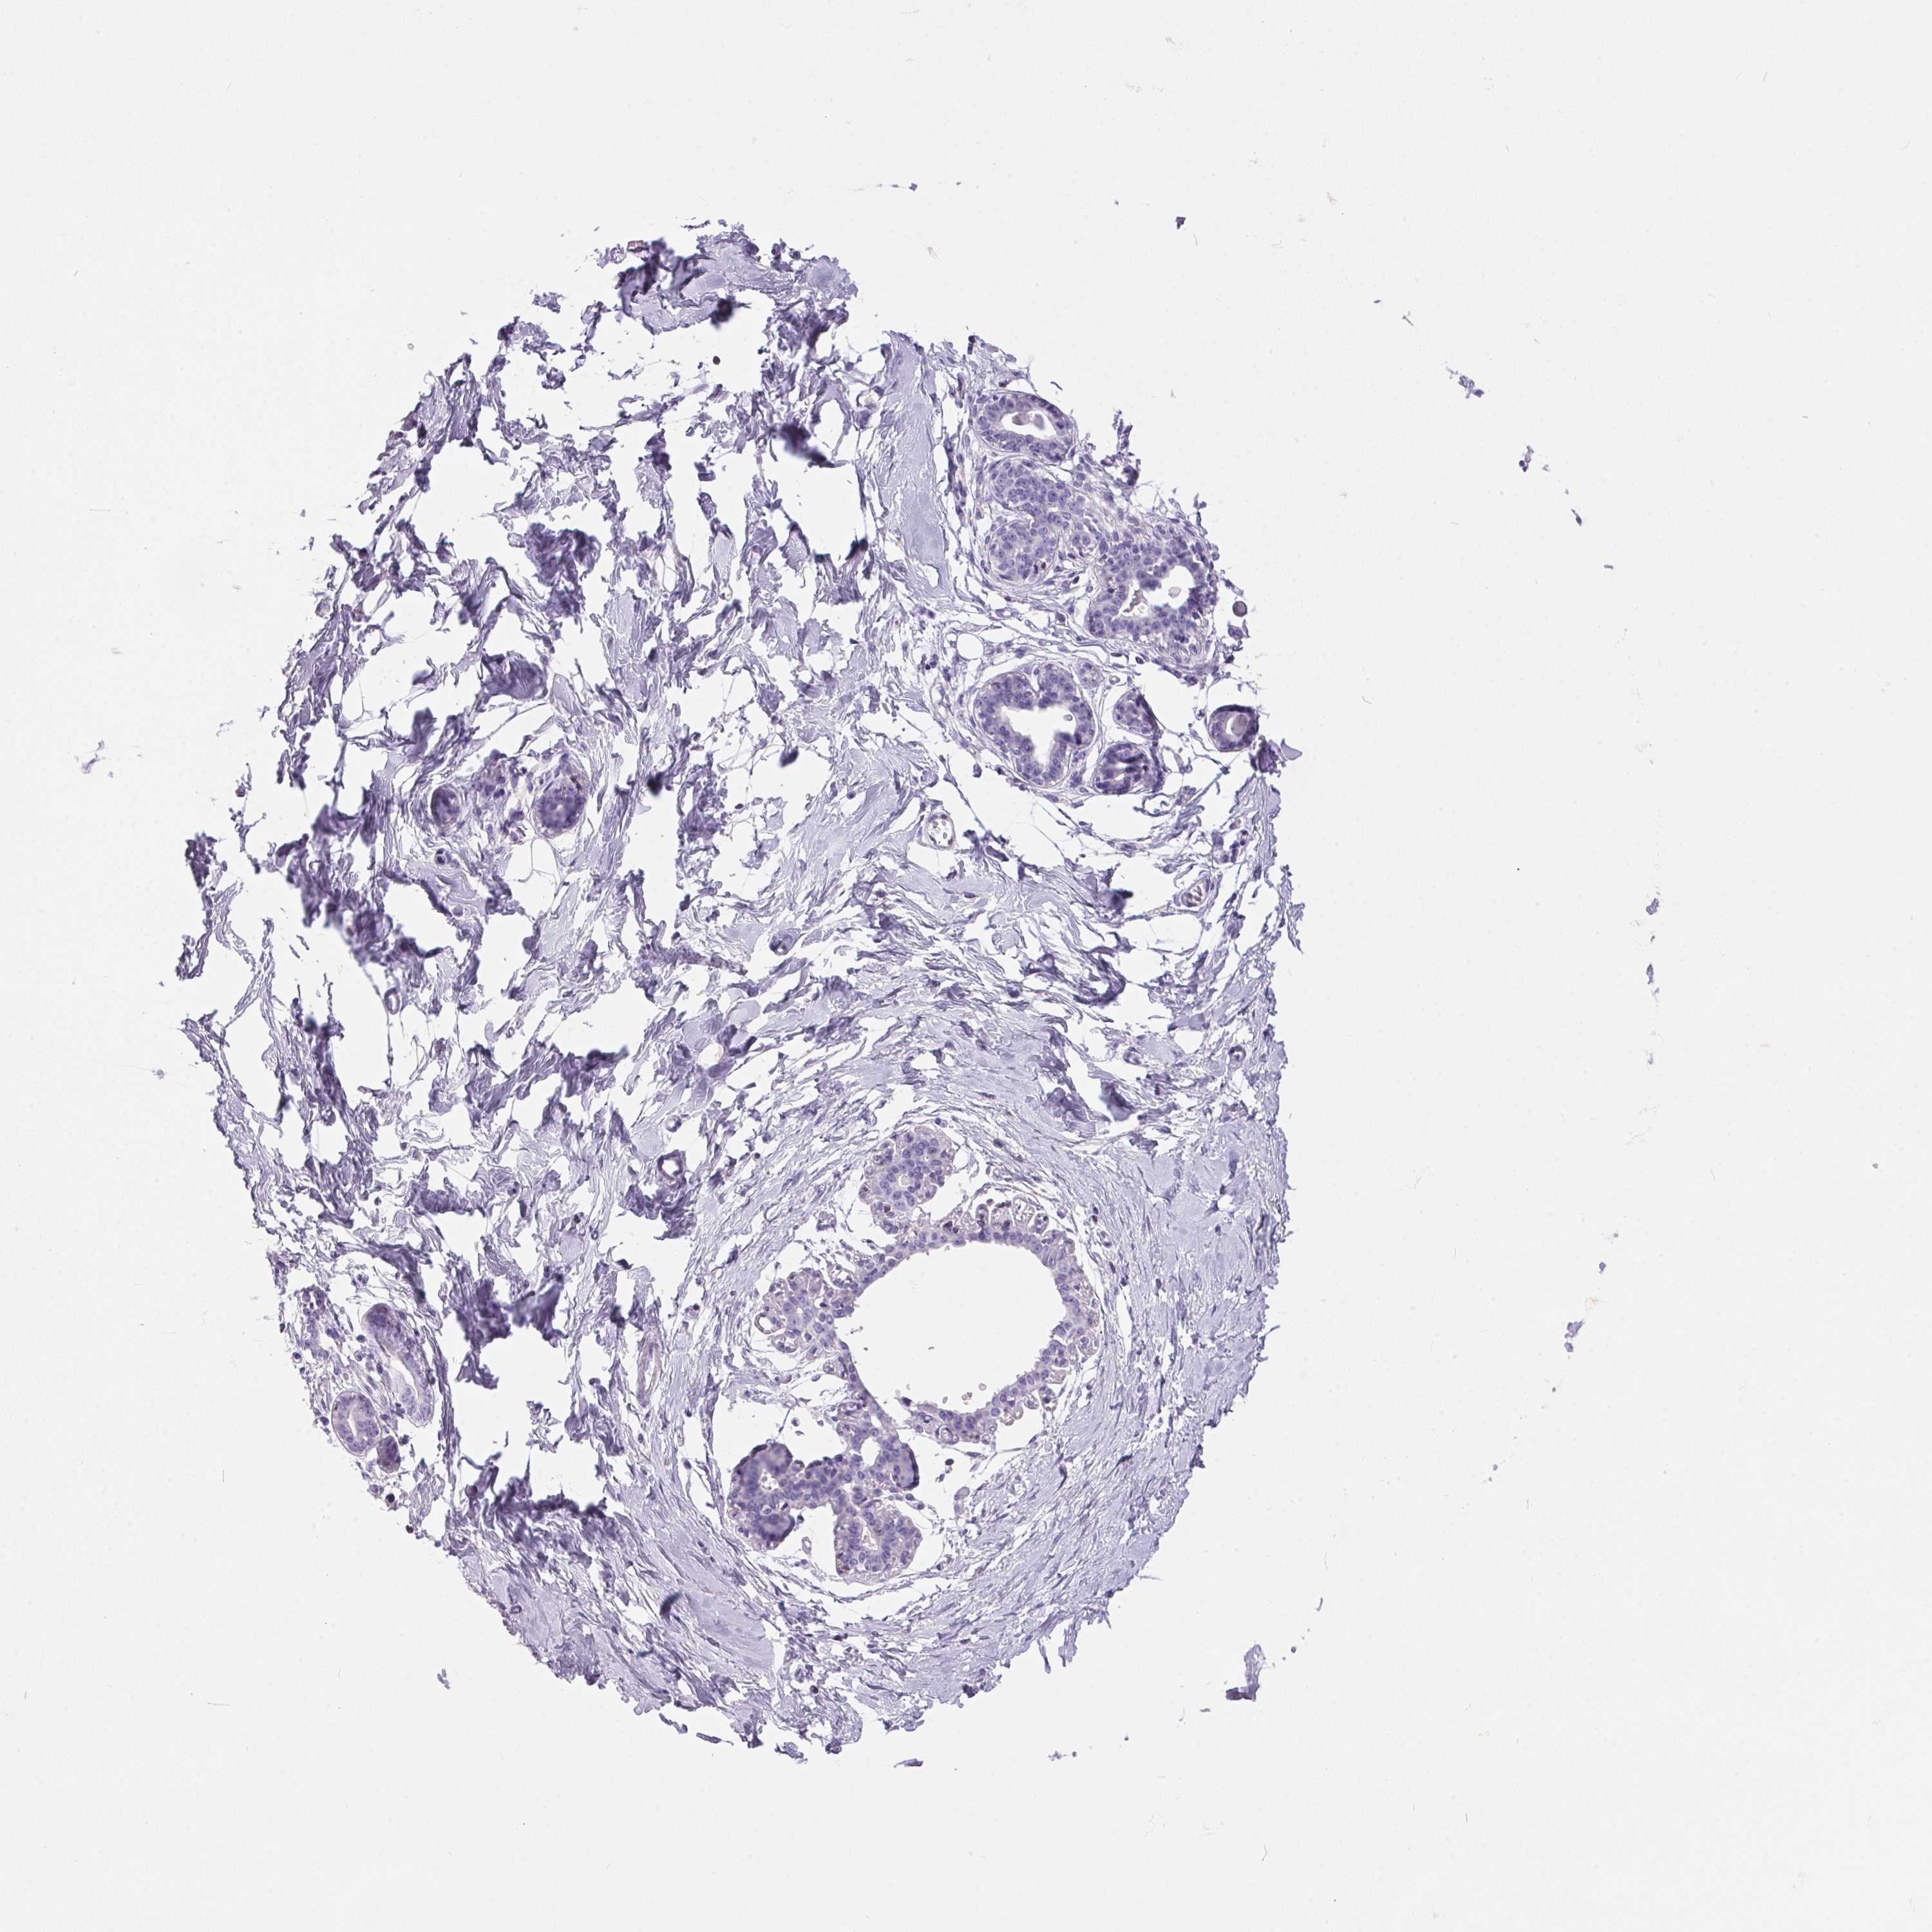

Antibody staining in the annotated cell types in the current human tissue is reported as not detected, low, medium, or high. This score is based on the staining intensity and fraction of stained cells.

Information about each individual sample is listed below, including gender, age, a tissue section image and estimated fractions of cell types. pTPM (transcripts per million) values give a quantification of the gene abundance which is comparable between different genes and samples.

Glandular cells: 5 Adipocytes: 15 Other cell types: 80

Female, age 47

Breast sample 405 pTPM: 5.6

Cell types%